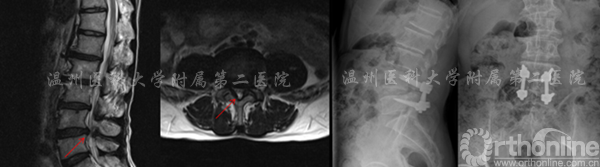

案例1

腰4/5腰椎管狭窄,行单节段CBT螺钉固定

术前MRI提示:腰4/5管狭窄(左) 术后X线提示:固定良好(右)